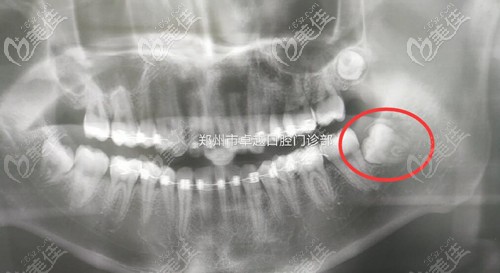

小伙们看,这是我的牙齿情况,整个智齿简直是睡在我的牙床里,这种长相不规律有自己想法的牙齿一般都是阻生智齿,因为位置不正,我的牙齿经常发炎,而且还压的我的大牙都歪斜了,所以这类的牙齿别拖,赶紧拔掉!